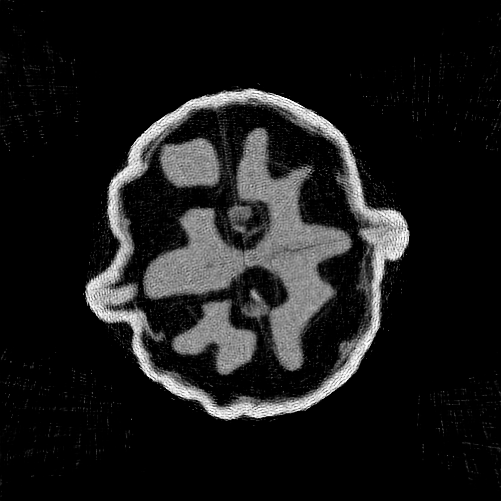

However, ensuring the reconstruction is of the best quality is not straightforward, as optimisation must be stopped before the network starts fitting the noise. This is illustrated in Figure 2, which shows a decrease in the loss function, quantifying data fidelity, over the entire optimisation trajectory. The best reconstruction, as measured by PSNR, is obtained relatively early in the optimisation (see the dashed vertical green line in Figure 2). We also show the reconstruction obtained by early stopping the optimisation process (see the dashed vertical red line in Figure 2) using the method by Wang et al. (2021), described in Section 4.1. This early stopped reconstruction is better than the final reconstruction (dashed vertical blue line in Figure 2), but there is still a gap to the peak PSNR. There is an even larger discrepancy between the highest PSNR attainable with DIP and the PSNR of the final reconstruction (using fully optimised network parameters). This form of overfitting poses a major challenge as the number of optimisation steps required to obtain the best reconstruction is not known a priori and strongly depends on the task, the neural network architecture, the noise level in the measurement data, and the used optimisation algorithm. Avoiding or mitigating overfitting has spurred significant research in the DIP community. An overview of these methods is provided in Section 4.

Refer to caption

Figure 2: Vanilla DIP on the μ\muCT walnut with 6060 angles and 128128 detector pixels. For details see the description in Section 6.